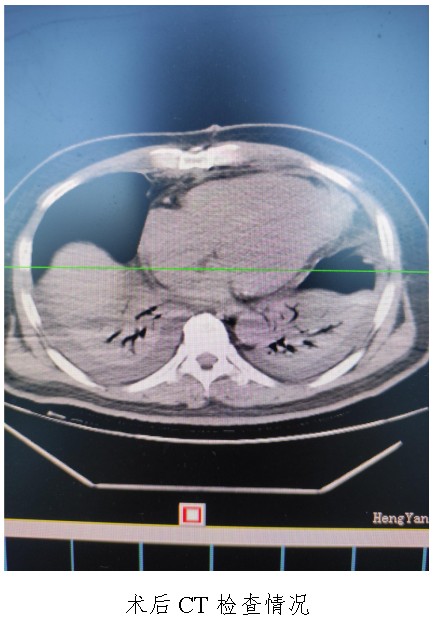

通訊員廖金文報(bào)道:一名50歲左心室前壁中下段及心尖部巨大室壁瘤患者在衡陽市中心醫(yī)院心胸外科廖金文主任、屈云劍副主任團(tuán)隊(duì)的精心治療下,接受左心室室壁瘤切除加左心室修補(bǔ)成型手術(shù)后,恢復(fù)良好,于11月1日出院。

10月18日,50歲的孟先生因反復(fù)胸悶氣促一周,夜間不能平臥來衡陽市中心醫(yī)院心胸外科就診,經(jīng)心臟超聲檢查提示左心室前壁中下段及心尖部巨大室壁瘤,66×57mm,最薄處約3mm?;颊哂卸嗄晏悄虿〔∈?,既往有無癥狀心肌梗死病史,曾行PCI治療。入科后,廖金文主任、屈云劍副主任組織心內(nèi)、麻醉、體外循環(huán)、重癥醫(yī)學(xué)科對(duì)病人病情進(jìn)行了多學(xué)科討論,一致認(rèn)為手術(shù)是治療該病例的唯一手段。經(jīng)過充分的術(shù)前準(zhǔn)備,10月24日,心臟外科團(tuán)隊(duì)給患者實(shí)施了左心室室壁瘤切除加左心室修補(bǔ)成型手術(shù),手術(shù)順利,術(shù)后經(jīng)過精心的治療管理,患者恢復(fù)良好,康復(fù)出院。該病例的手術(shù)成功,不僅是術(shù)中及手術(shù)團(tuán)隊(duì)智慧的結(jié)晶,也是多學(xué)科合作的結(jié)果,展示了衡陽市中心醫(yī)院處理復(fù)雜危重患者的能力。